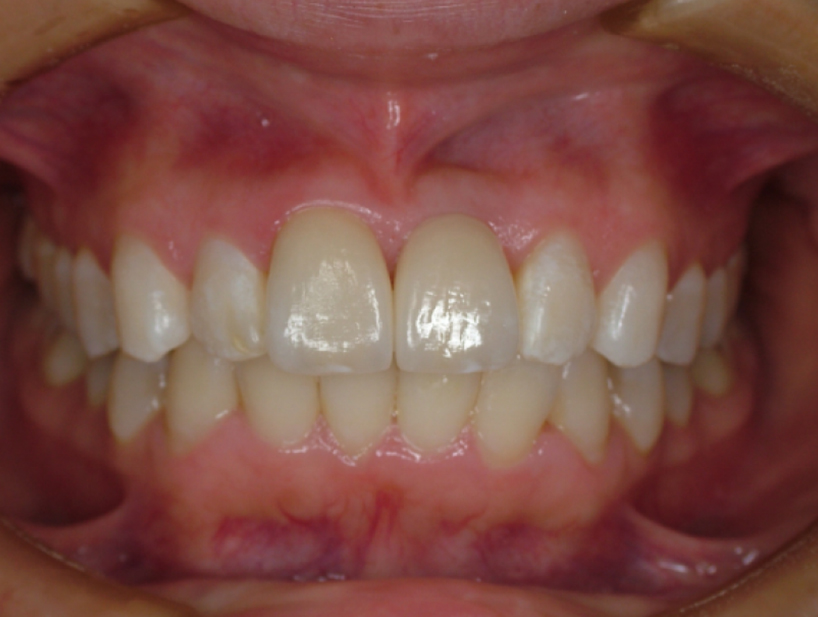

治療前治療後

| 治療内容 | 前歯インプラント治療/下前歯矯正治療 |

|---|---|

| 患者様の年齢 | 19歳 |

| 患者様の性別 | 女性 |

| 治療期間 | 1年 |

| 治療回数 | 矯正治療合わせて45回程度 |

| 治療費用 | インプラント治療50万円/矯正15万円 |